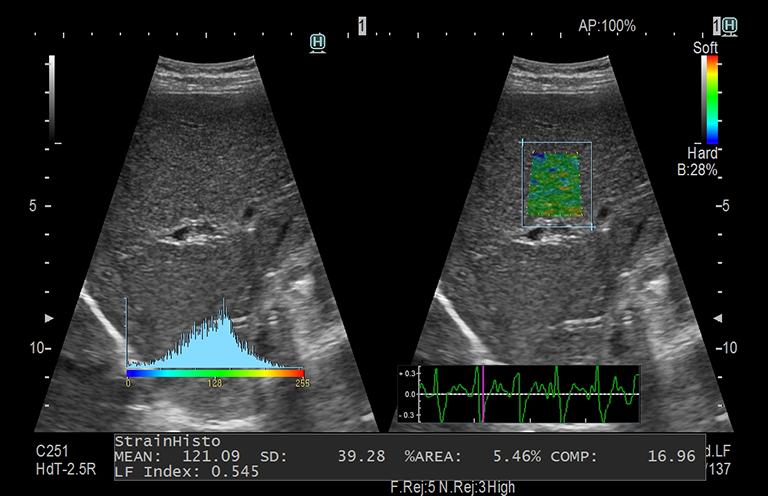

Aplicación: Abdomen

Función/análisis: ÍNDICE LF

Comentarios: Hígado